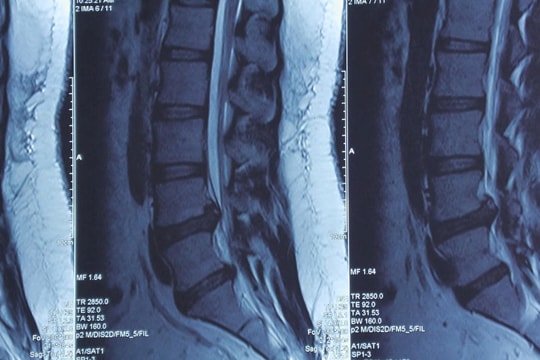

Cô gái 23 tuổi suýt liệt chân vì thoát vị đĩa đệm